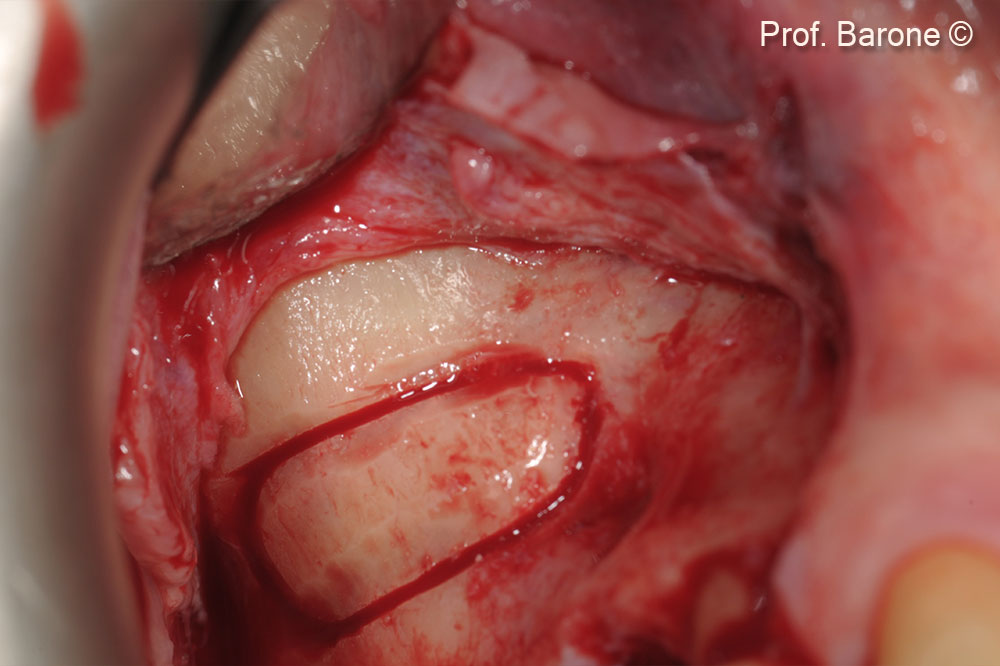

Surgical access to the antero-lateral bone wall

Osteotomy window performed with surgical ultrasounds